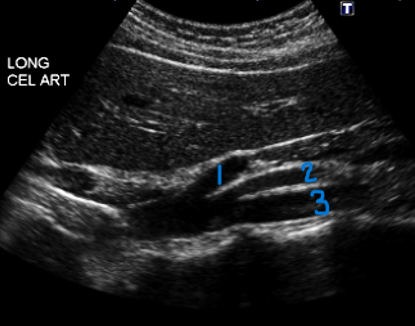

<p>In this sagittal view, what is #1?</p>

In this sagittal view, what is #1?

Splenic Vein

<p>In this sagittal view, what is #2?</p>

In this sagittal view, what is #2?

Celiac Trunk

<p>In this sagittal view, what is #3?</p>

In this sagittal view, what is #3?

SMA

<p>In this sagittal view, what is #4?</p>

In this sagittal view, what is #4?

Aorta